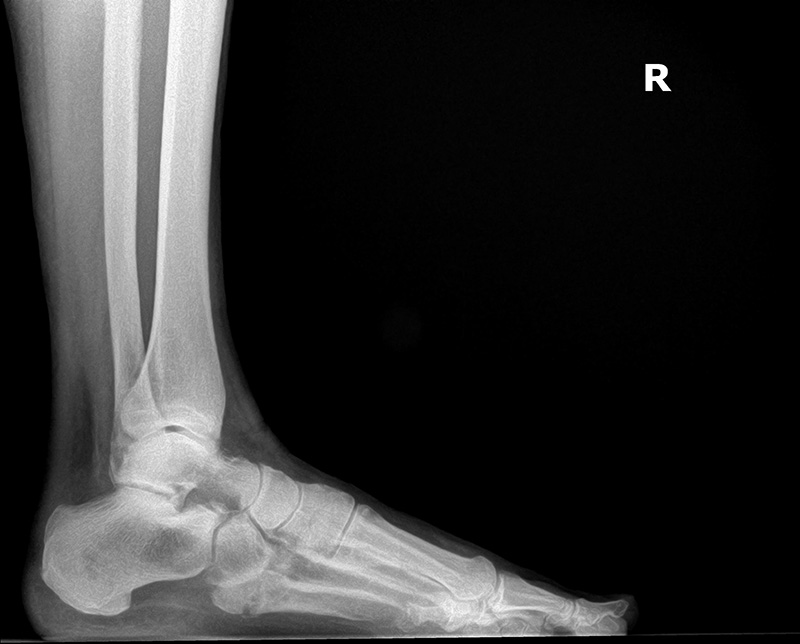

Initial Lateral View to post 4 week lateral view